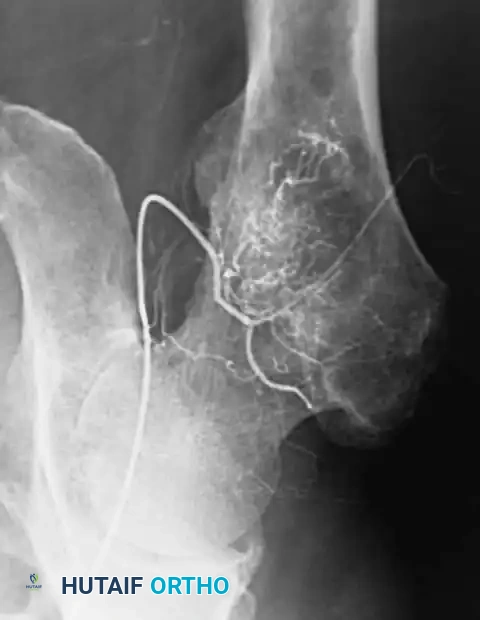

Preoperative Optimization and Embolization

Highly cellular marrow-replacing tumors (including lymphoma, myeloma, and renal/thyroid metastases) can be massively vascular. If open reduction or extensive exposure is anticipated, preoperative angiography and embolization should be strongly considered to mitigate catastrophic intraoperative hemorrhage.

Preoperative angiogram demonstrating a highly vascular tumor blush in the proximal femur.